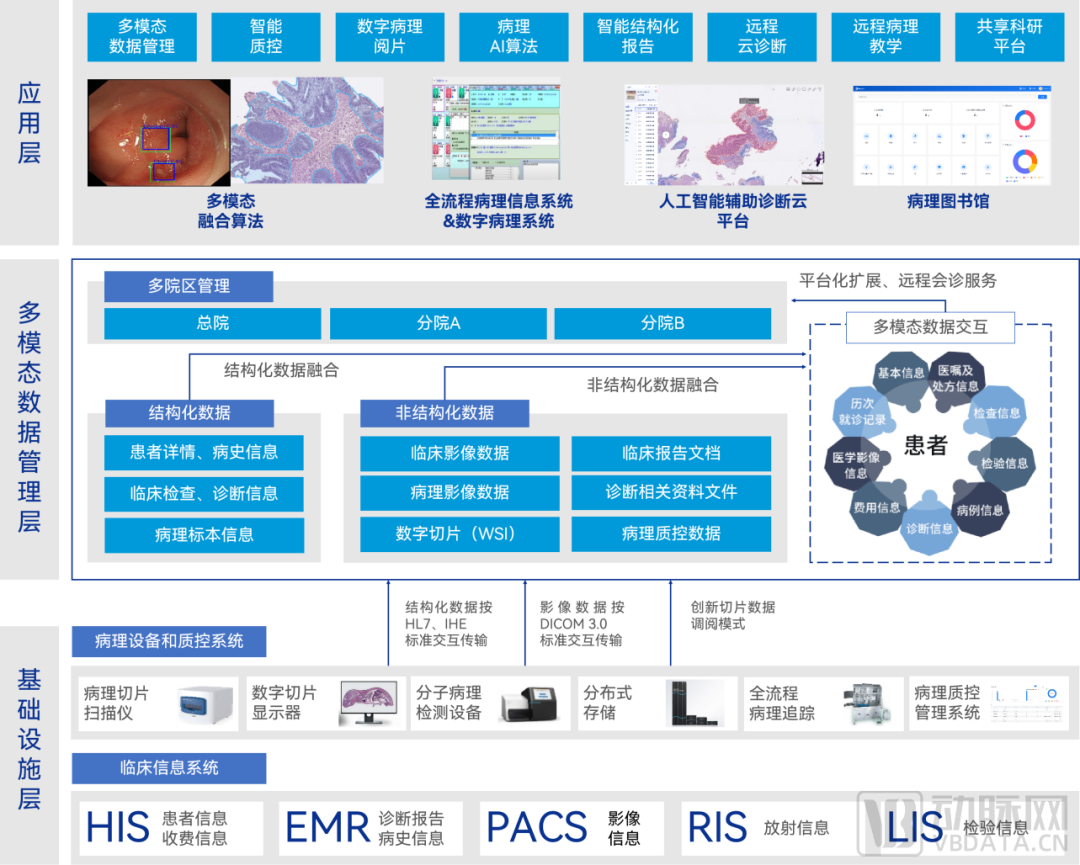

数字化智慧病理科建设全景图

来源:蛋壳研究院